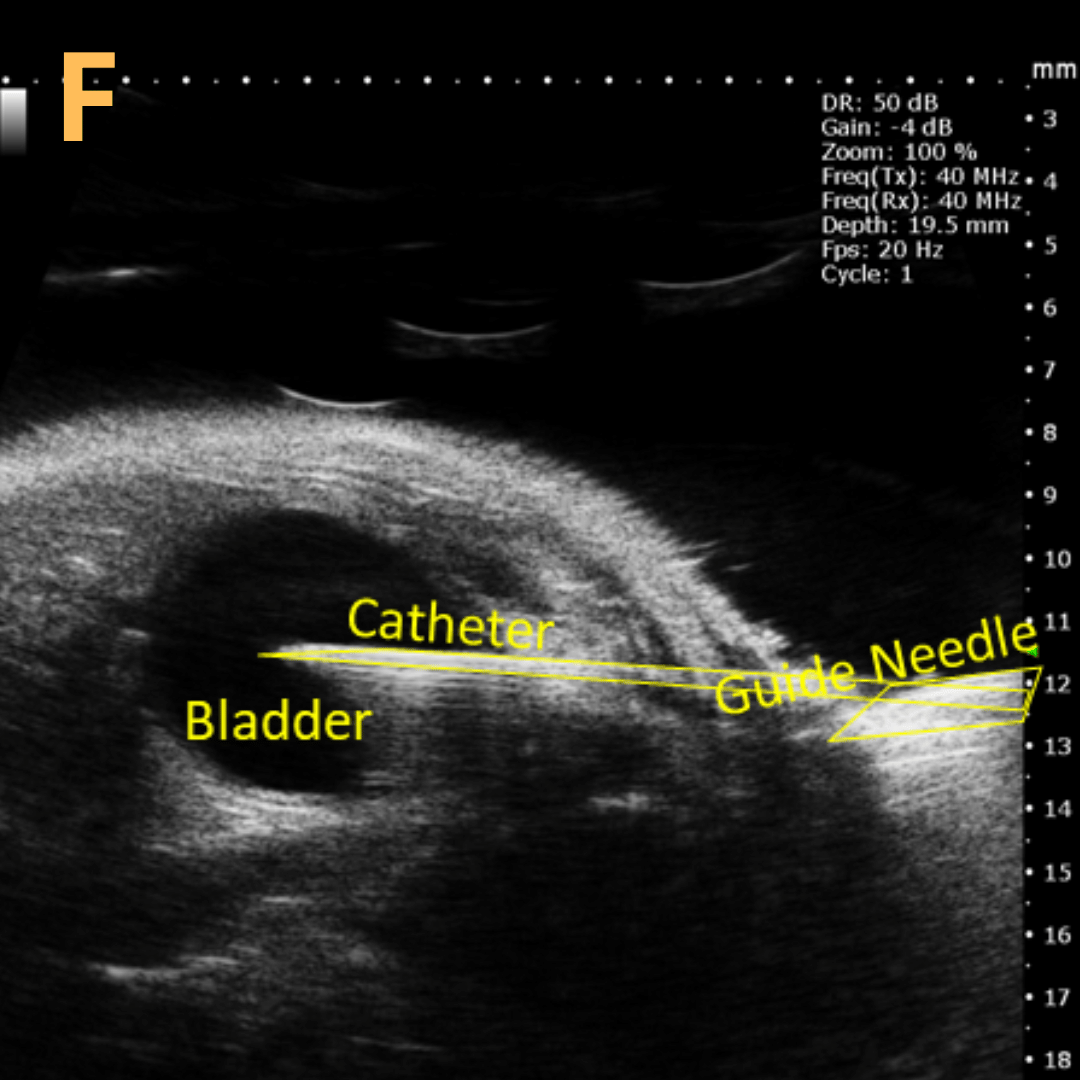

Ultrasound-Guided Bladder Catheterization

This is A) a B-mode video showing insertion of a thin-needle catheter via a larger-sized guide needle with B) the landmarks noted. C) is another example of this technique with D) the landmarks noted. E) Removal of catheter needle with F) the landmarks noted. Verification of successful injection via catheter is shown in G – H with G) showing the bladder before injection and H) showing after successful injection. Imaging on a wildtype C57B6J mouse model – acquired images are from Stephen Zderic’s lab at the Children’s Hospital of Philadelphia.

An in-plane introducer (guide) needle was used to puncture through the skin of the animal, while a thin needle catheter was fed through the introducer needle and used to puncture through the bladder wall. Using the catheter prevents potential leakage or complete collapse of bladder.